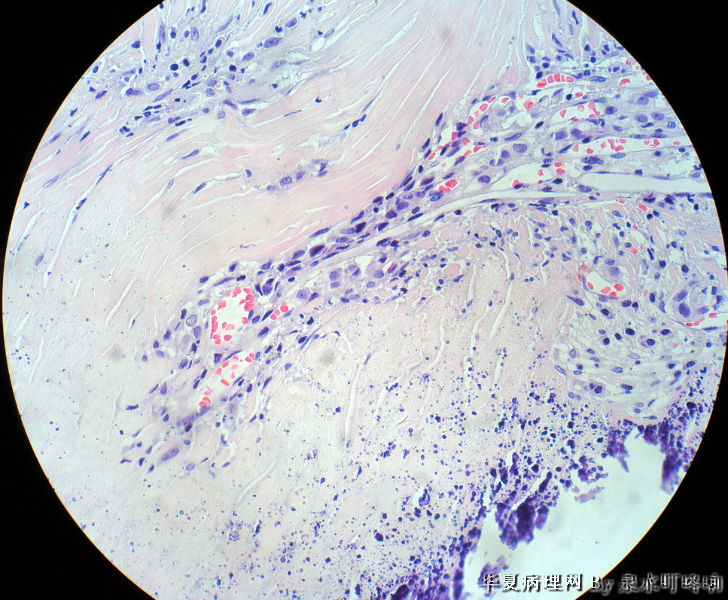

120212,女,55岁,左颈部肿物七年余。

大体:灰白肿物一个,大小约2.1×1.5×1.3厘米。表面光滑,包膜完整,切面灰白,部分包膜有钙化。

与手术医生沟通,肿物位于左颈部靠近甲状腺部位,比较浅(门诊手术),手术医生认为是淋巴结部位。